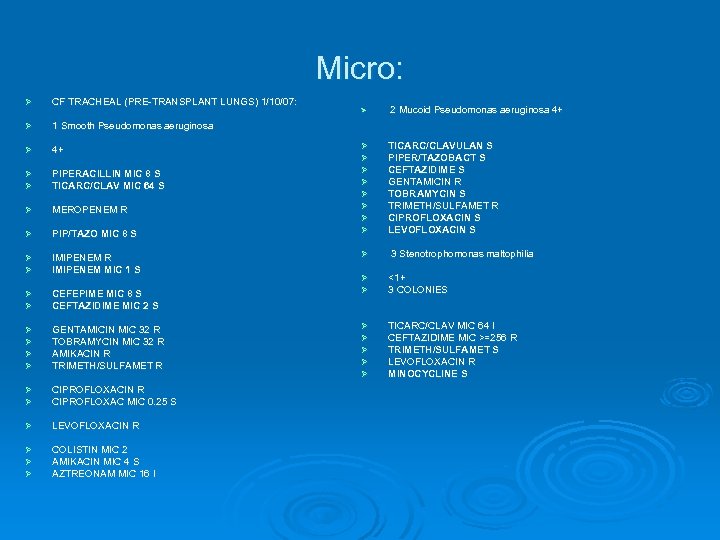

Micro: Ø CF TRACHEAL (PRE-TRANSPLANT LUNGS) 1/10/07: Ø 1 Smooth Pseudomonas aeruginosa Ø 4+ Ø Ø PIPERACILLIN MIC 8 S TICARC/CLAV MIC 64 S Ø MEROPENEM R Ø PIP/TAZO MIC 8 S Ø Ø IMIPENEM R IMIPENEM MIC 1 S Ø Ø CEFEPIME MIC 8 S CEFTAZIDIME MIC 2 S Ø Ø GENTAMICIN MIC 32 R TOBRAMYCIN MIC 32 R AMIKACIN R TRIMETH/SULFAMET R Ø Ø CIPROFLOXACIN R CIPROFLOXAC MIC 0. 25 S Ø LEVOFLOXACIN R Ø Ø Ø COLISTIN MIC 2 AMIKACIN MIC 4 S AZTREONAM MIC 16 I Ø Ø Ø Ø Ø 2 Mucoid Pseudomonas aeruginosa 4+ TICARC/CLAVULAN S PIPER/TAZOBACT S CEFTAZIDIME S GENTAMICIN R TOBRAMYCIN S TRIMETH/SULFAMET R CIPROFLOXACIN S LEVOFLOXACIN S 3 Stenotrophomonas maltophilia Ø Ø <1+ 3 COLONIES Ø Ø Ø TICARC/CLAV MIC 64 I CEFTAZIDIME MIC >=256 R TRIMETH/SULFAMET S LEVOFLOXACIN R MINOCYCLINE S